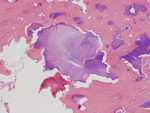

There was a temporary improvement in her jaw symptoms, but after 5 to 7 days, infection with purulent discharge returned. Follow-up imaging, including a panoramic radiograph (Figure 3), showed persistent mottled, mixed irregular radiolucent-radiopaque appearance, slightly more extensive than that seen on the previous panoramic image. The third debridement of the wound was performed 10 weeks after extraction of the root of the third molar, which was 6 weeks after the first debridement and 3.5 weeks after the second debridement and on day 43 of the oral clindamycin. A large amount of granulation tissue and multiple sequestra of devitalized bone were curetted out down to vital-appearing (bleeding) bone. A second culture and sensitivity test did not reveal the presence of microorganisms. The biopsy was positive for “necrotic sclerotic bone with acute osteomyelitis and colonies of filamentous bacterial organisms consistent with actinomycetes” (Figure 4). As actinomycotic organisms are present in the normal oral flora, the existence of actinomycetes is not an indication of “actinomycosis.” In addition, these features seen under the microscope do not clearly distinguish chronic osteomyelitis from BRONJ.

Next, it is known that as the treatment of chronic osteomyelitis progresses, the surrounding vital healthy bone develops a protective involucrum and undergoes the remodeling process with a slow return of the typical trabecular pattern of bone. This was seen in the described case (Figure 4). Presence of a vital surrounding bone was also confirmed clinically every time the debridement procedure was performed. BRONJ treatment often does not show signs of remodeling and separation due to presence of permanently affected avascular bone in the entire jaw. In BRONJ cases, the entire skeleton is affected by the drug-related condition (often called chemonecrosis). The morning fasting serum C-terminal cross-linking telopeptide (CTX), an index of bone turnover that can help to identify the degree of BRONJ, was not tested in the presented case.